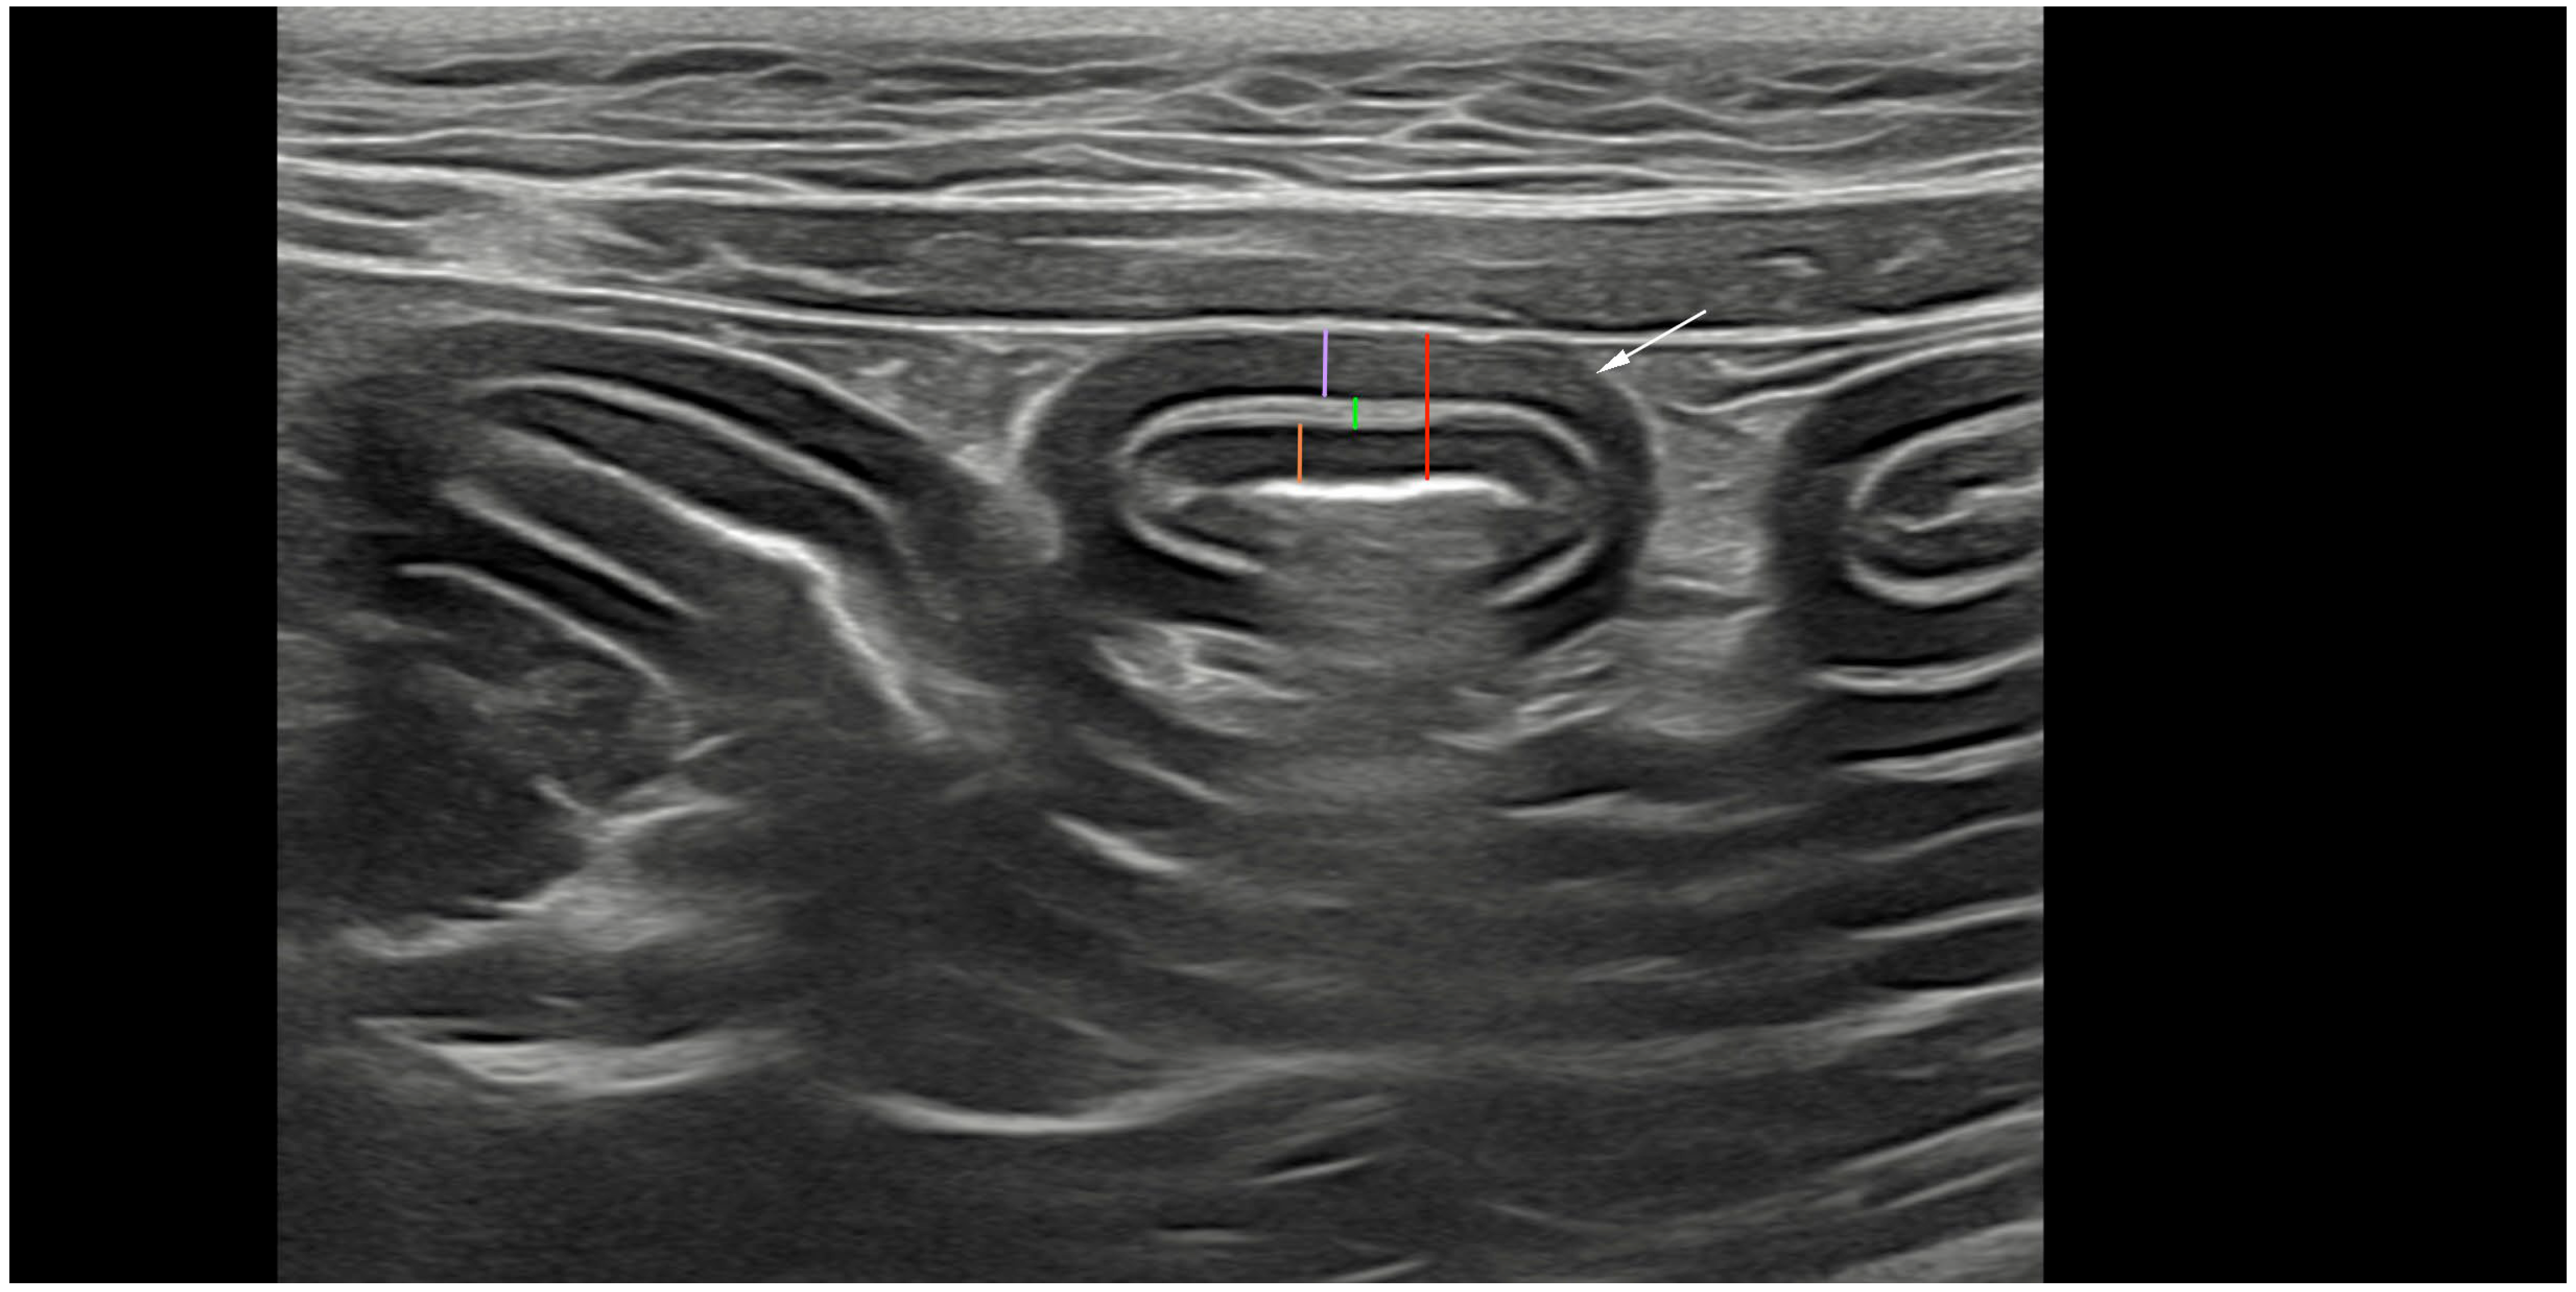

2.2. Ultrasonography and Analyses

3.3. Ultrasonographic Measurements